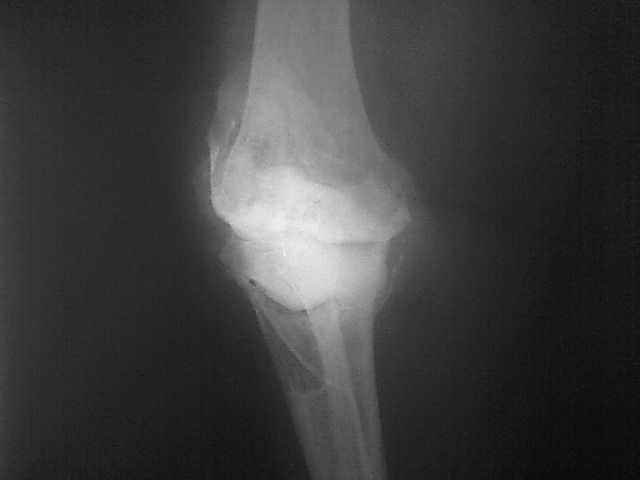

Уважаемые коллеги, прошу Вашего совета по тактике лечения. Женщина 1952 г.р., оперирована в

2006, в одной клинике установлен эндопротез правого коленного сустава, через год

нестабильность обоих компонентов, доктор выполняет ревизию обычным протезом с задним

стабилизатором. В октябре 2008 - нестабильность, свищ. В другом стационаре все удалено,

спейсер с гентамицином, длинный курс антибиотиков.

Коллатеральных связок нет. Собственная связка надколенника цела. До удаления протеза -

Имя     : 29.01.09.jpg

Тип     : image/jpeg

Размер  : 10337 байтов

Описание: отсутствует

Url     : http://weborto.net:8080/pipermail/ortho/attachments/20090219/242fe889/attachment-0005.jpg